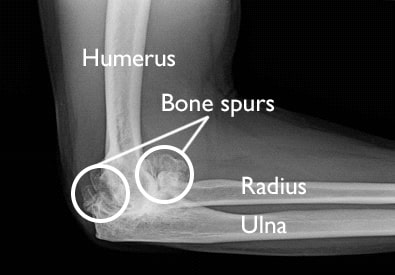

x-ray of elbow osteoarthritis

This X-ray of an elbow taken from the side shows severe osteoarthritis. Note the large bone spurs that have formed around the joint. During an arthroscopic procedure, these bone spurs can be removed, along with any loose fragments of cartilage.